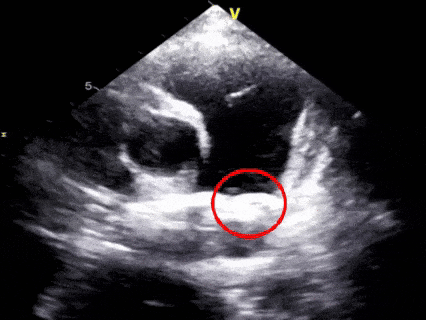

术前超声再次确认

动脉水平可见明显彩色血流

胸骨旁主动脉短轴切面